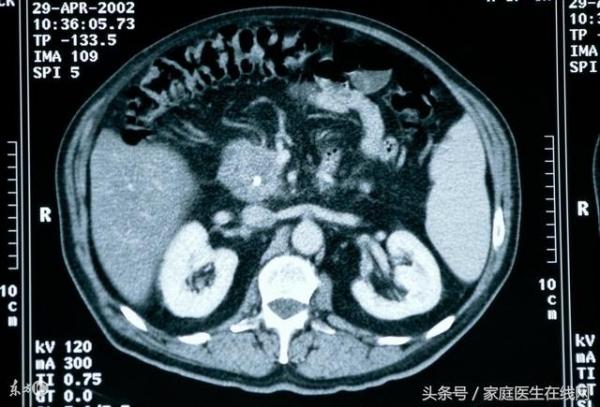

診斷性檢查可考慮CT掃描,不依賴手術,

不受病人體形和胃腸道氣體的限製,

可確定肝臟轉移灶、淋巴病變和周圍血管侵犯,

但對小於2Cm 的損害或腹膜小結節的診斷不可靠;